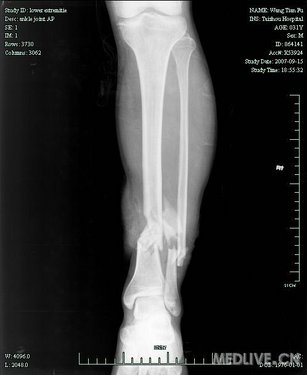

胫腓骨骨折

辅助检查: X线正位片应包括胫腓骨全长,以免漏诊。X线可见骨折线、碎骨片、断端移位等。